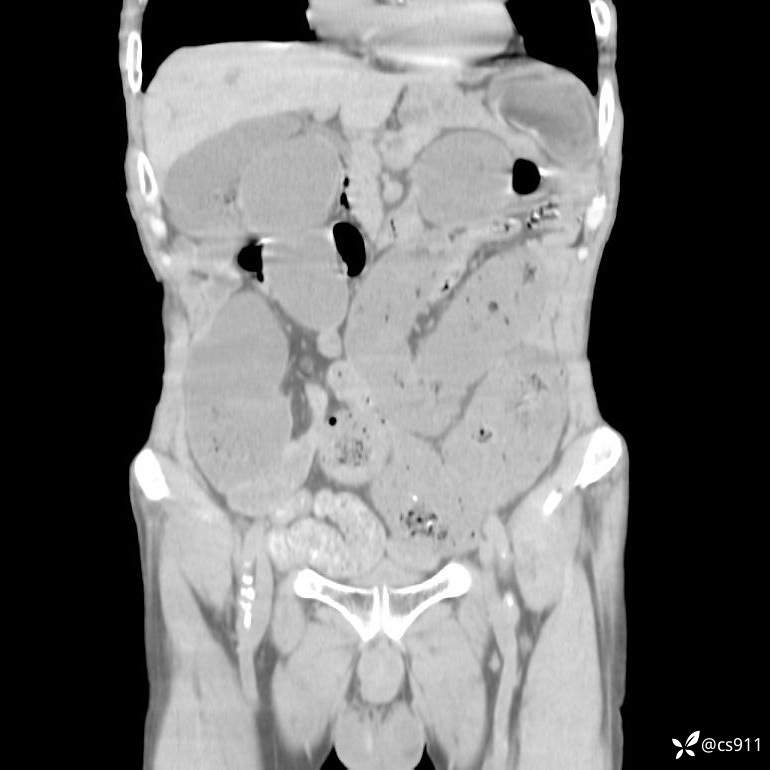

急腹症之急诊CT,原因?答案公布

男,77岁,腹痛、腹胀伴恶心呕吐1天。呕吐胃内容物,非喷射性呕吐,有咖啡色样胃内容物,诉有胃穿孔病史。查体:全腹平,下腹部压痛,全腹无反跳痛,叩诊呈浊音,移动性浊音阴性,肠鸣音减弱,1-2次/分。肛检:直肠未扪及明显肿物,可触及大量粪块。

T 36.6℃ P 80次/分 R 26次/分 BP 100/60mmHg

白细胞(WBC) H 14.55 10e9/L 4-10

中性粒细胞百分率(NEUT%) H 85.7 % 40-75

血淀粉酶(AMY) HH 1859 U/L 35-135

癌胚抗原(CEA) H 27.44 ng/ml 0-5

呕吐物 潜血试验 * 阳性 阴性

患者轮椅入室检查神志清楚, 能配合摆位和呼吸